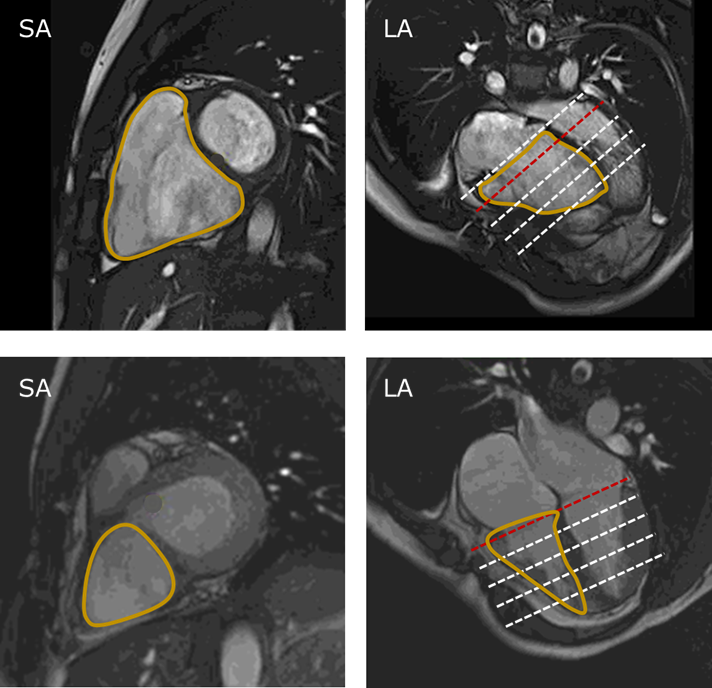

M&Ms-2 Challenge, CBAR-UNet: A novel methodology for segmentation of cardiac

CBAR-UNet: A novel methodology for segmentation of cardiacエアコン用コンピュータボード回路基板 2D16DA1 ボード良好な動作